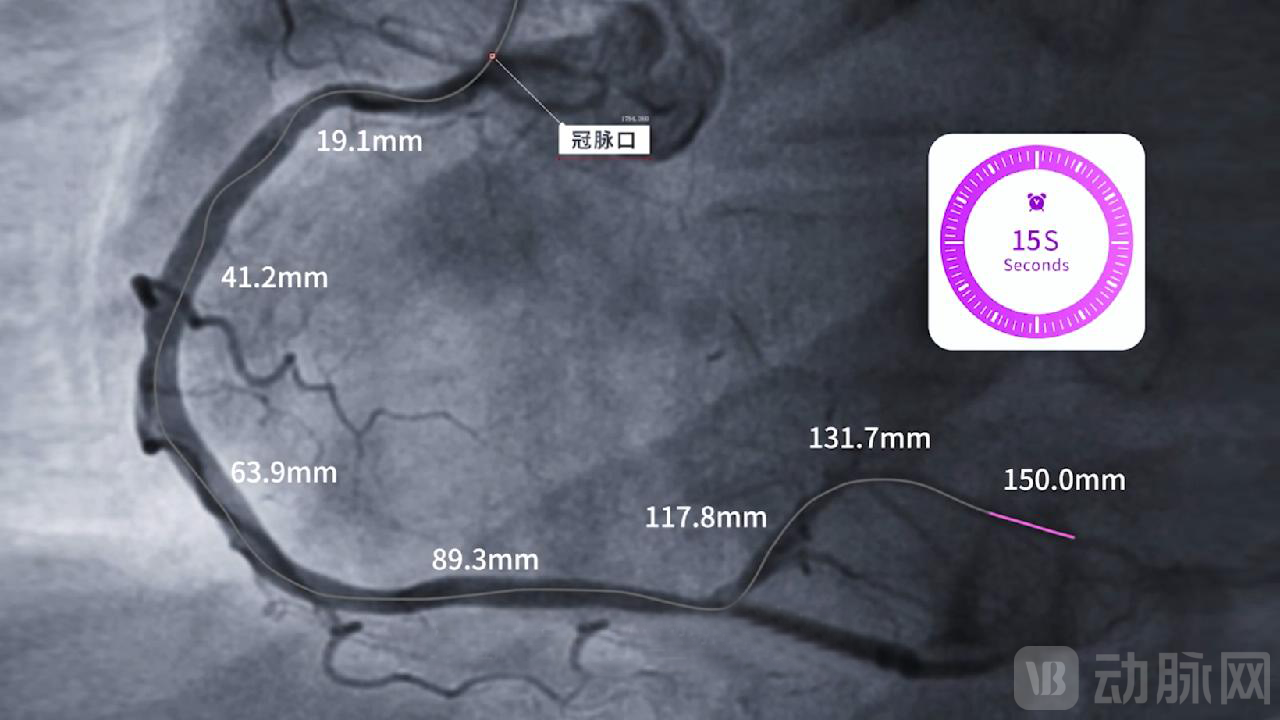

2、高速

北芯血管内超声成像系统,多达4档不同回撤速度,满足不同临床使用场景;最高100Fps成像帧频,长轴方向致密扫描,不错过任何微小病变信息;当以最快的速度10毫米每秒进行回撤时,取得150毫米长度的病变信息仅需15秒,大幅缩短腔内影像检查时间的同时,极大降低了由于导管长时间滞留病变血管所引起的血管痉挛、心肌缺血等手术风险,使腔内影像检查更快速、更安全。

3、高效

北芯TRUEVISION®系列导管,拥有150毫米的超长回撤距离;病变查看范围覆盖全血管,尤其针对弥漫性病变或串联病变,仅一次回撤便可获得全部病变信息,避免了多次回撤和操作模式切换所需的额外操作和时间,提升手术效率,优化手术流程。